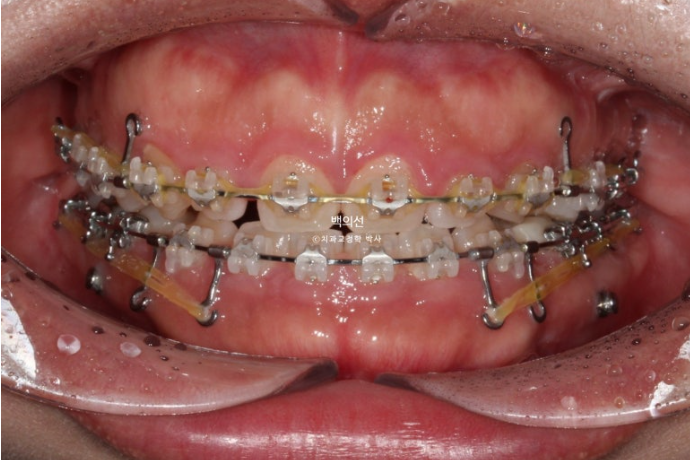

치료 시작 1년째 사진입니다.

24.07

발치공간 폐쇄, 앞니 후방이동, 거미스마일 해소와 하관길이 및 무턱의 해소를 위한 전체치열 함입을 진행합니다.